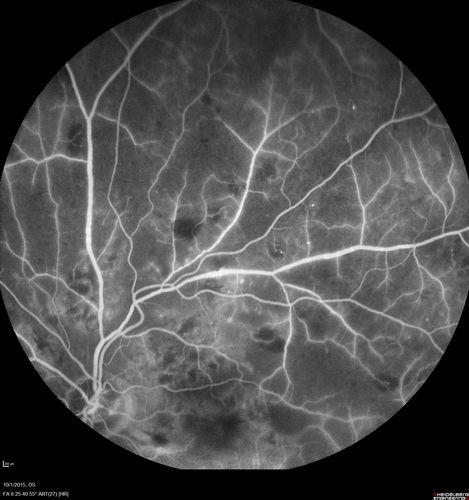

Hairy Cell Leukemia - Retinal Hemorrhage and twig Branch Vein Occlusion

79 year old man He has had hairy cell leukemia since 2002.  He is in remission.  His last blood tests were 9/2018.  He just moved down here and needs a new leukemia doctor.  His vision is fine.

VA OD: Dcc20/25

VA OS: Dcc20/25

IOP: TP: OD:12 OS:12